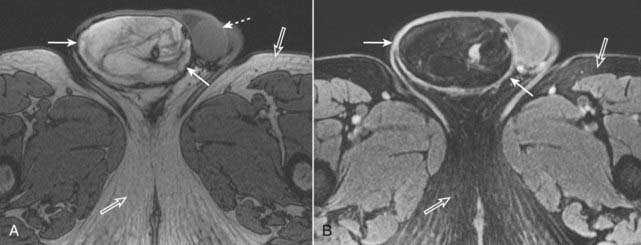

Figure 20-9 Fat in a liposarcoma of the right spermatic cord.

A, Axial T1-weighted image of the scrotum demonstrates a bright, heterogeneous right scrotal mass (solid white arrows). The left testis is unremarkable (dotted white arrow), and the right testis is not visualized. Note that subcutaneous fat is normally bright (open white arrows). B, Axial T1-weighted, fat-suppressed, gadolinium-enhanced image demonstrates that the bright signal in the right scrotal mass is now dark, consistent with fat (solid white arrows). The subcutaneous fat of the thighs is also dark (open white arrows). This was an unusual malignancy of the spermatic cord derived from fat cells.